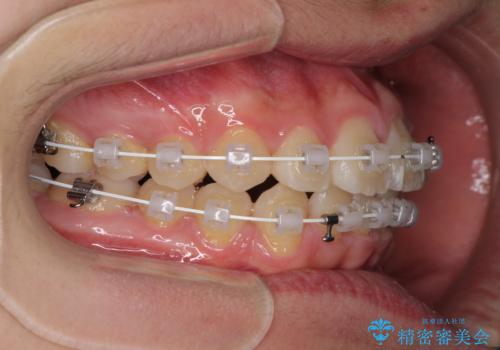

前歯のデコボコを短期間で治療 目立たないワイヤー矯正

- 矯正装置

- 審美装置

- 上下前歯のデコボコを改善したいとのことで来院された患者様です。

自己管理を減らしたいとのことで、ワイヤー装置による矯正治療を行うこととしました。

中学生と言うこともあり、1年強の短期間で終了しました。

歯磨きがしっかりとできないと虫歯になるリスクがありましたが、治療期間中は清潔な状態を保っていただけました。